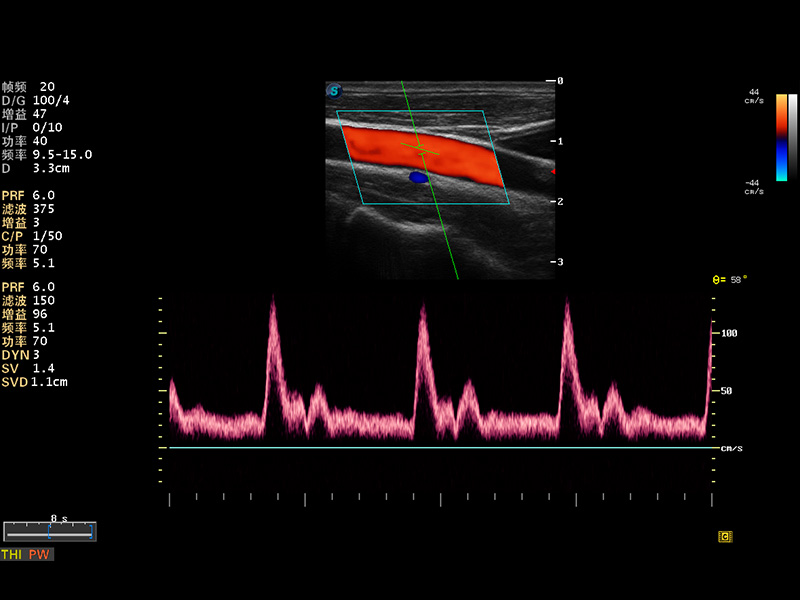

S8 EXP便携式彩色多普勒超声诊断仪是亚星官网研发的高端全身应用型便携彩超。高通道的VIS平台融合可视化(Visual)、智能化(Intelligent)和人性化(Smart)的特点,配以亚星官网自主研发生产的探头大家族,使您能够快速、准确的获得病人信息,提高工作效率的同时减轻疲劳。

成像技术

多波束形成器

μ-Scan微米成像

谐波成像

实时宽景成像

空间复合成像

3D/4D成像